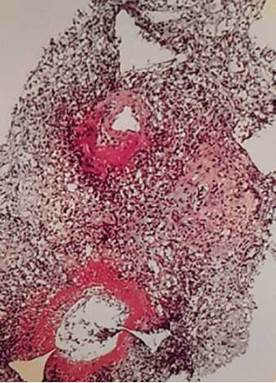

After expanding the spectrum of diagnostic tests to confirm the clinical suspicion, an autoimmunity study was performed. It was positive for perinuclear myeloperoxidase antineutrophil cytoplasmic antibodies (MPO-ANCA), with a 1/80 dilution. A Doppler ultrasound of temporal arteries was also performed and was normal (Figure 4). However, in view of the existing involvement, and since the confirmatory diagnosis of vasculitis is anatomopathological, a kidney biopsy was performed in which the presence of an arterial vessel with fibrinoid necrosis and associated infiltration of polymorphonuclear cells was observed. These are clear signs of active microscopic polyangiitis (MPA) vasculitis (Figure 5).

Source: Document obtained during the course of the study.

Figure 5 Kidney biopsy showing an arterial vessel with fibrinoid necrosis and associated polymorphonuclear infiltrates suggestive of microscopic polyangiitis.